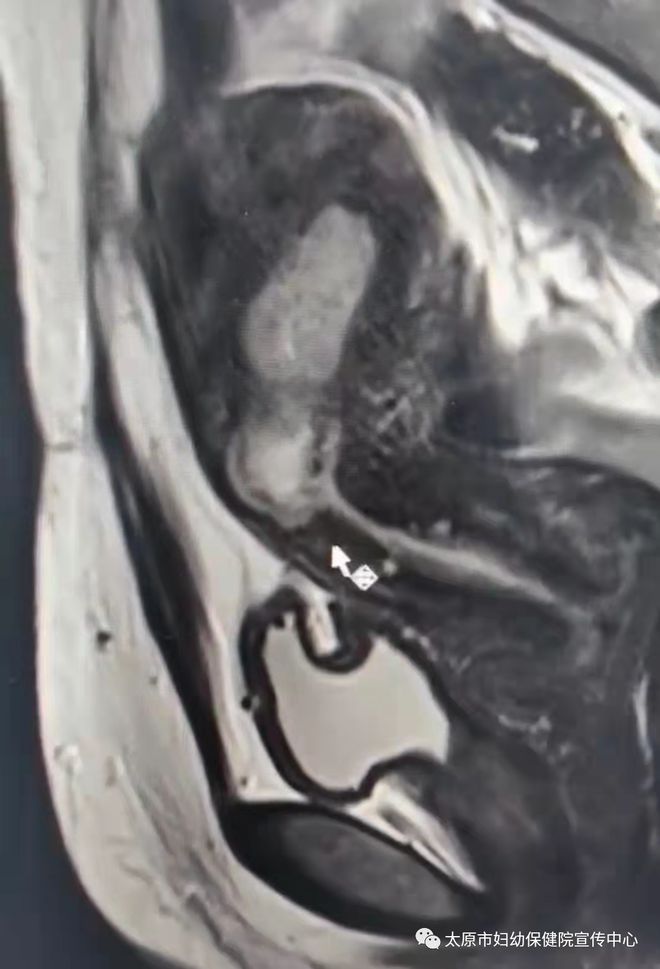

(MRI:箭头所指为瘢痕妊娠处)

当天,妇科医师团队进行讨论会诊,认真分析患者病情,结合她的盆腔核磁,明确妊囊完全位于剖宫产切口处憩室腔内,该处肌层部分断裂消失,距离浆膜层仅仅2mm,清宫术中大出血风险性极高,甚至有子宫穿孔损伤膀胱可能。在与患者及家属充分沟通后,放射影像科主任李志强为王女士行子宫动脉介入术。